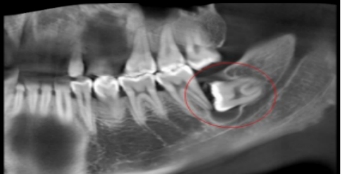

阻生牙(impacted teeth)是指部分萌出或完全不能萌出,且以后也不会自行萌出的牙。好发部位为下颌第三磨牙、上颌第三磨牙及上颌尖牙,其中阻生第三磨牙也叫做阻生智齿。

5、邻牙及支持组织的吸收:当阻生的智齿萌出过程中受阻于第二磨牙时,会引发第二磨牙牙根牙根逐渐吸收,严重者可使下颌第二磨牙远中牙根完全吸收,致第二磨牙松动、疼痛,常常食物嵌塞发生慢性牙周炎,也会造成牙槽骨的炎症性吸收,使第二磨牙反复肿痛。